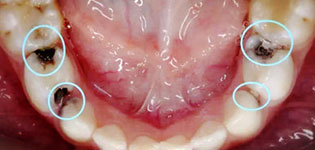

正常牙齿与牙齿之间,排列得十分紧密,邻近的牙齿移动后,牙齿与牙齿会出现缝隙,容易使食物嵌塞到牙齿间隙里,引起口臭、龋齿、牙周病等。